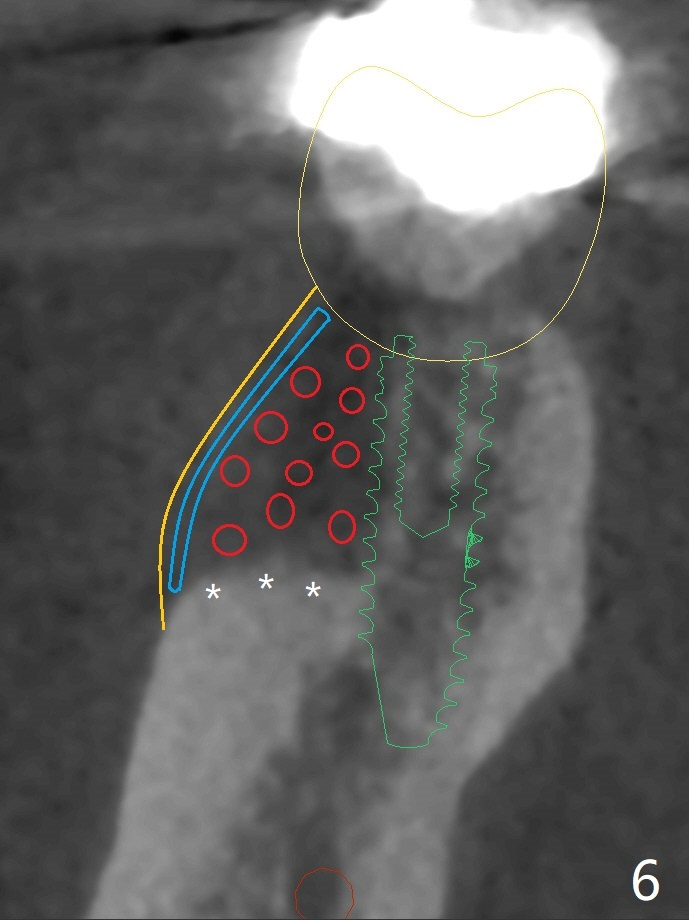

A 47-year-old man has poor dentition. The tooth #31 needs RCT, while #30 has severe PARL, especially mesial (Fig.1 M). The buccal roots are exposed (Fig.2). Between the exposed roots is the septal gingiva, which will be saved for buccal soft tissue repair (Fig.3 *). The septal gingiva will keep in place (not to be transferred) so that the recession will disappear by epithelial regrowth from the nearby gingiva (Fig.3' arrows) over the bone graft and PRF. The provisional should be fabricated to cover the soft tissue defect (Fig.3'' yellow area). In fact the mesial root fractures (Fig.4 ^), as related to the severe bony defect. There seems to be enough lingual bone to hold a 4x13 mm implant (Fig.5 green). Sticky bone (Fig.6 red circles) and PRF (blue) are to be used to repair the hard and soft tissue defects following an immediate provisional (Fig.5,6 yellow outline). Extra layer of acrylic (Fig.6 orange) will be used to cover the PRF buccally. The base of the buccal plate is thick (Fig.6 *); mesial portion appears to be denser (Fig.7 black *) than the distal one (white *). Decortication will be done if hemorrhage is insufficient. Fig.8 is a coronal section of the socket (B: buccal). Extraction (Fig.9 black area) will most likely result in a knife edge ridge. Extraction with bone graft may not fare better, as it is easy to lose the graft considering missing buccal hard and soft tissues.